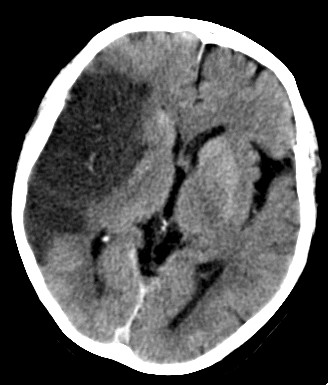

El TC sin contraste es una herramienta diagnóstica de gran valor por su disponibilidad, rapidez y por la no administración de contraste iv. Nos permite identificar la presencia de hemorragia así como la presenciad de signos precoces de infarto, que son los siguientes:

4- Borramiento de surcos de la convexidad: Por pérdida de la diferenciación sustancia gis – sustancia blanca en la convexidad. Mismo concepto, los surcos corticales dejan de observarse y no se puede distinguir la sustancia gris de la blanca debido el edema citotóxico lesional.

Para observar un proceso isquémico deberíamos ajustar la ventana: 40/40; 40/20; 30/10; serían buenos ejemplos que permiten aumentar la sensibilidad hasta el 70%. De este modo, adecuamos el contraste para diferenciar mejor el tejido normal del edematoso.